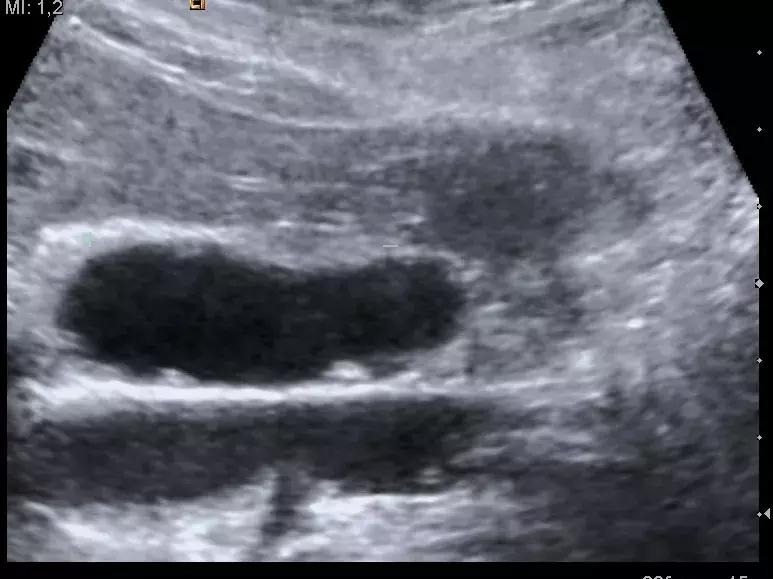

B超检查

胆囊息肉没有特异的临床表现,大约1/6的病人没有不适症状,仅在B超检查时偶然被发现,而其余大多数病人也仅有右上腹胀痛等酷似慢性胆囊炎或胆石病的临床表现。B超诊断胆囊息肉的准确性明显高于CT,更优于胆囊造影术。

此外,B超还能清晰地显示胆囊息肉的部位、大小哦、数目,以及局部胆囊壁的变化。因此,B超是诊断胆囊息肉既简便又可靠的检查方法,且具有较高的临床诊断价值。尤其是不伴胆囊结石者,B超诊断胆囊息肉的准确率极高。